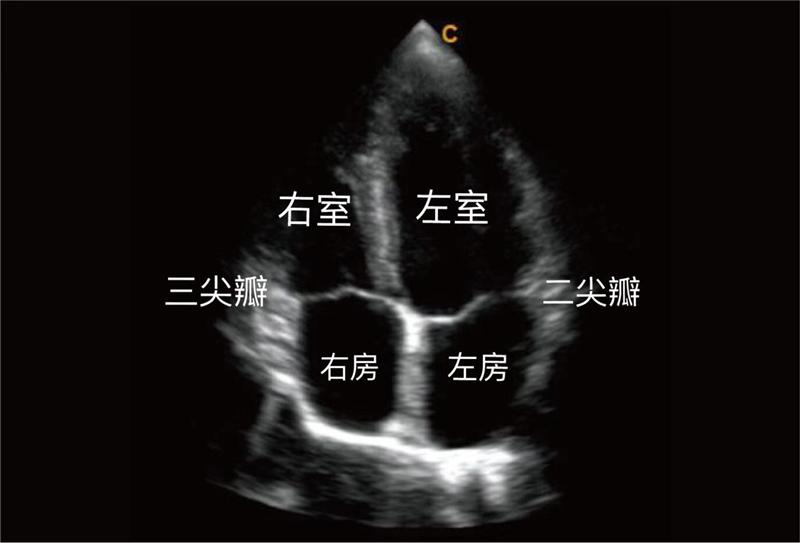

首先让我们来认识一下心脏的基本结构,心脏有四个腔室:左房、左室;右房、右室以及瓣膜。心脏有四个瓣膜,就像阀门。三尖瓣就是位于右房与右室之间的瓣膜,它引导血液由右房进入右室。如果一部分血液流错了方向就会出现返流。

正常胎儿三尖瓣返流,大多为轻度,返流量少,峰值返流速度小于2m/s,返流束长度较短,局限于右房近端1/3,返流束面积占右房面积的30%以下,无心脏或心外畸形,属于正常的生理性返流。其中,中孕期的发生率最高,而且大部分病例随着孕周的增加而消失。所以对于中孕期发现三尖瓣返流的胎儿,除了细致的观察心脏结构,在晚孕期甚至出生后的动态观察也是非常必要的。